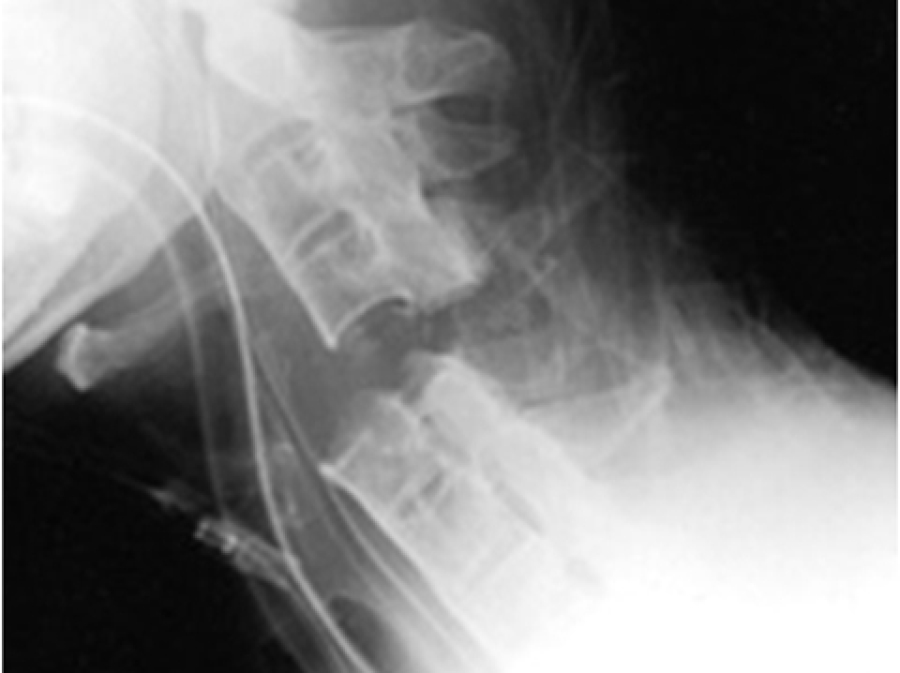

Learn MoreElective Spinal Disease

Degenerative spinal disease, atlantoaxial subluxation, spondylolisthesis and spondylitis

Learn MoreSpinal Trauma

Acute spinal injury management including spinal cord injury management both acutely and in the longer term. There are some complimentary sessions in the rehabilitation module.